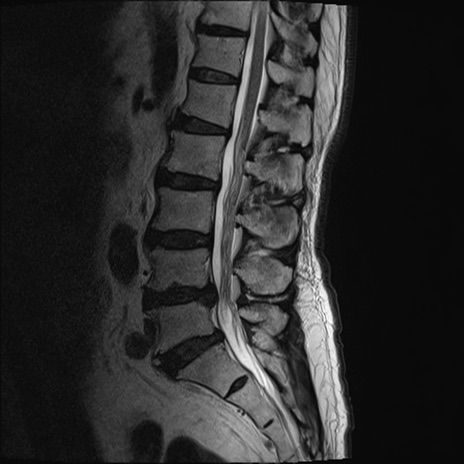

【整形】TIPS症例2 腰椎MRI T2WI(矢状断像)

【症例】70歳代男性

【主訴】左下肢痛

【現病歴】2週間前くらいから腰痛、左下肢痛あり。左臀部から大腿、下腿外側のしびれが常時ある。歩行とともに同部位の痛みあり。

【身体所見】Lasegue70-/60+、Bragard-/±、PTR ±/±、ATR -/-、IP 5/5、TA 5/4、TS 5/5、EHL 右第1足趾なし/3、FHL 5/5、hypersthesia(-)、足背動脈触知良好

異常所見と診断は?